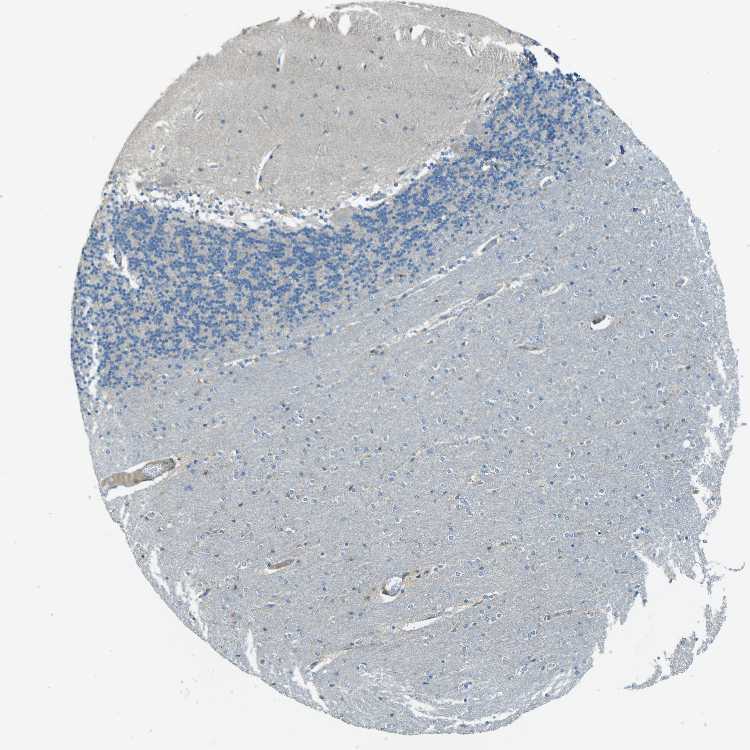

BRAIN CEREBELLUM Show tissue menu

CEREBELLUM - Antibody stainingi

Antibody staining in the annotated cell types in the current human tissue is reported as not detected, low, medium, or high, based on conventional immunohistochemistry profiling in selected tissues. This score is based on the combination of the staining intensity and fraction of stained cells.

Each image is clickable and will lead to virtual microscopy that enables deeper exploration of all samples and also displays staining intensity scores, fraction scores and subcellular localization as well as patient and tissue information for each sample.

Antibody HPA012820

Purkinje cells Medium

Cells in granular layer Low

Cells in molecular layer Not detected